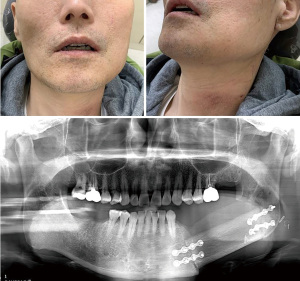

By enabling a transoral or retroauricular approach even in cases requiring the transcervical approach, or mandibulotomy with lip split, robotic surgery can reduce functional damage and decrease blood loss based on criteria such as the number of transfusions or mean drain stay (16). The length of hospital stay, chyle leak, hematoma, nerve weakness, seroma, wound infections and wound drainage have been evaluated in order to compare the postoperative course of robot assisted surgeries with conventional ones. According to a meta-analysis by Sukato et al. (17), there was no difference in the morbidity of local complications between robotic and conventional groups, nor was there a statistically significant difference in length of hospital stay. In addition, the incision line distant from the surgical site has clear advantages during radiotherapy (Figure 1).

Scar reduction is imperative, not only in flap insetting, but also in flap harvesting, and is feasible with robots (36,37). Using robots to harvest radial forearm free flaps can provide superior postoperative outcome in terms of both aesthetics and complications (Figure 1). Robot-assisted maxillofacial surgery with free flap reconstruction is reported to yield no statistically significant difference compared to conventional approaches in the morbidity of postop infection, drain time and ICU or hospital stay (16).